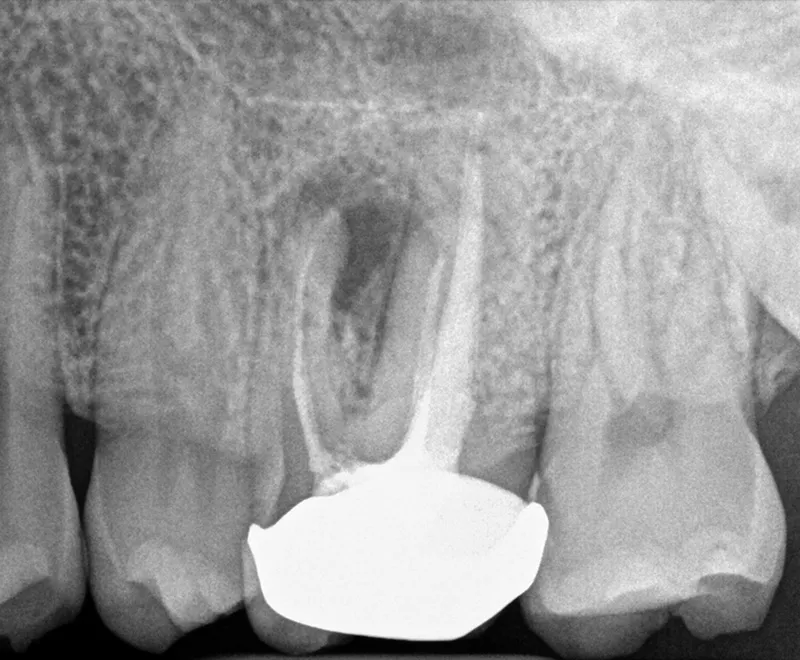

Image

Root canal retreatment before

Before